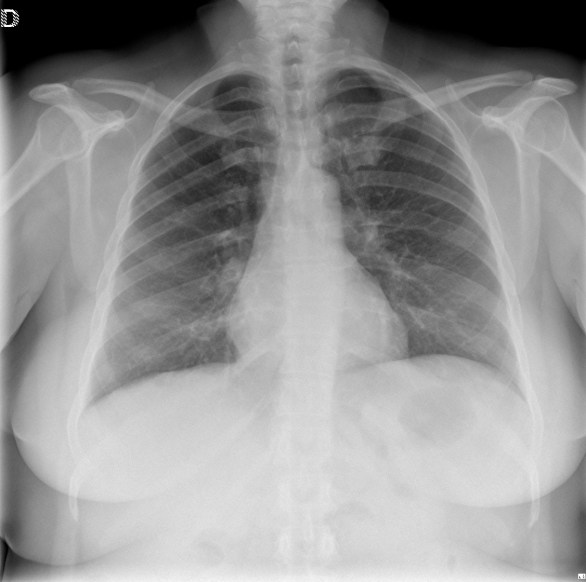

CASO: sospecha de neumonía.

Hallazgos:

- En un principio podríamos decir que existe un aumento de densidad retrocardiaco que podría ser compatible con condensación neumónica a dicho nivel, sin embargo estamos ante una placa poco inspirada, lo cual puede llevarnos a cometer errores diagnósticos.

- Se recomendó volver a realizar la radiografía, observar a continuación:

Ya no se observa el aumento de densidad retrocardiaco, la placa es normal.

INSPIRACIÓN: Una placa bien inspirada es aquella en la que se observar 6-7 arcos costales anteriores o 10-11 arcos costales posteriores. Lo contrario puede producir imágenes falsas de condensaciones o de seudocardiomegalia.